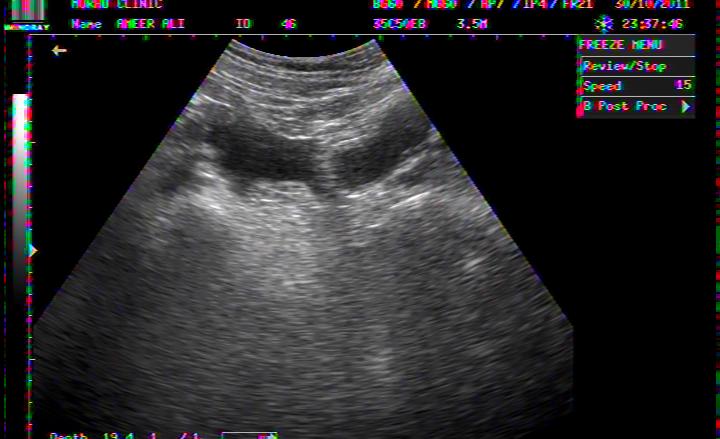

FLUID AROUND LIVER IN DHF

PLASMA FLUID AROUND LIVER IN DHF